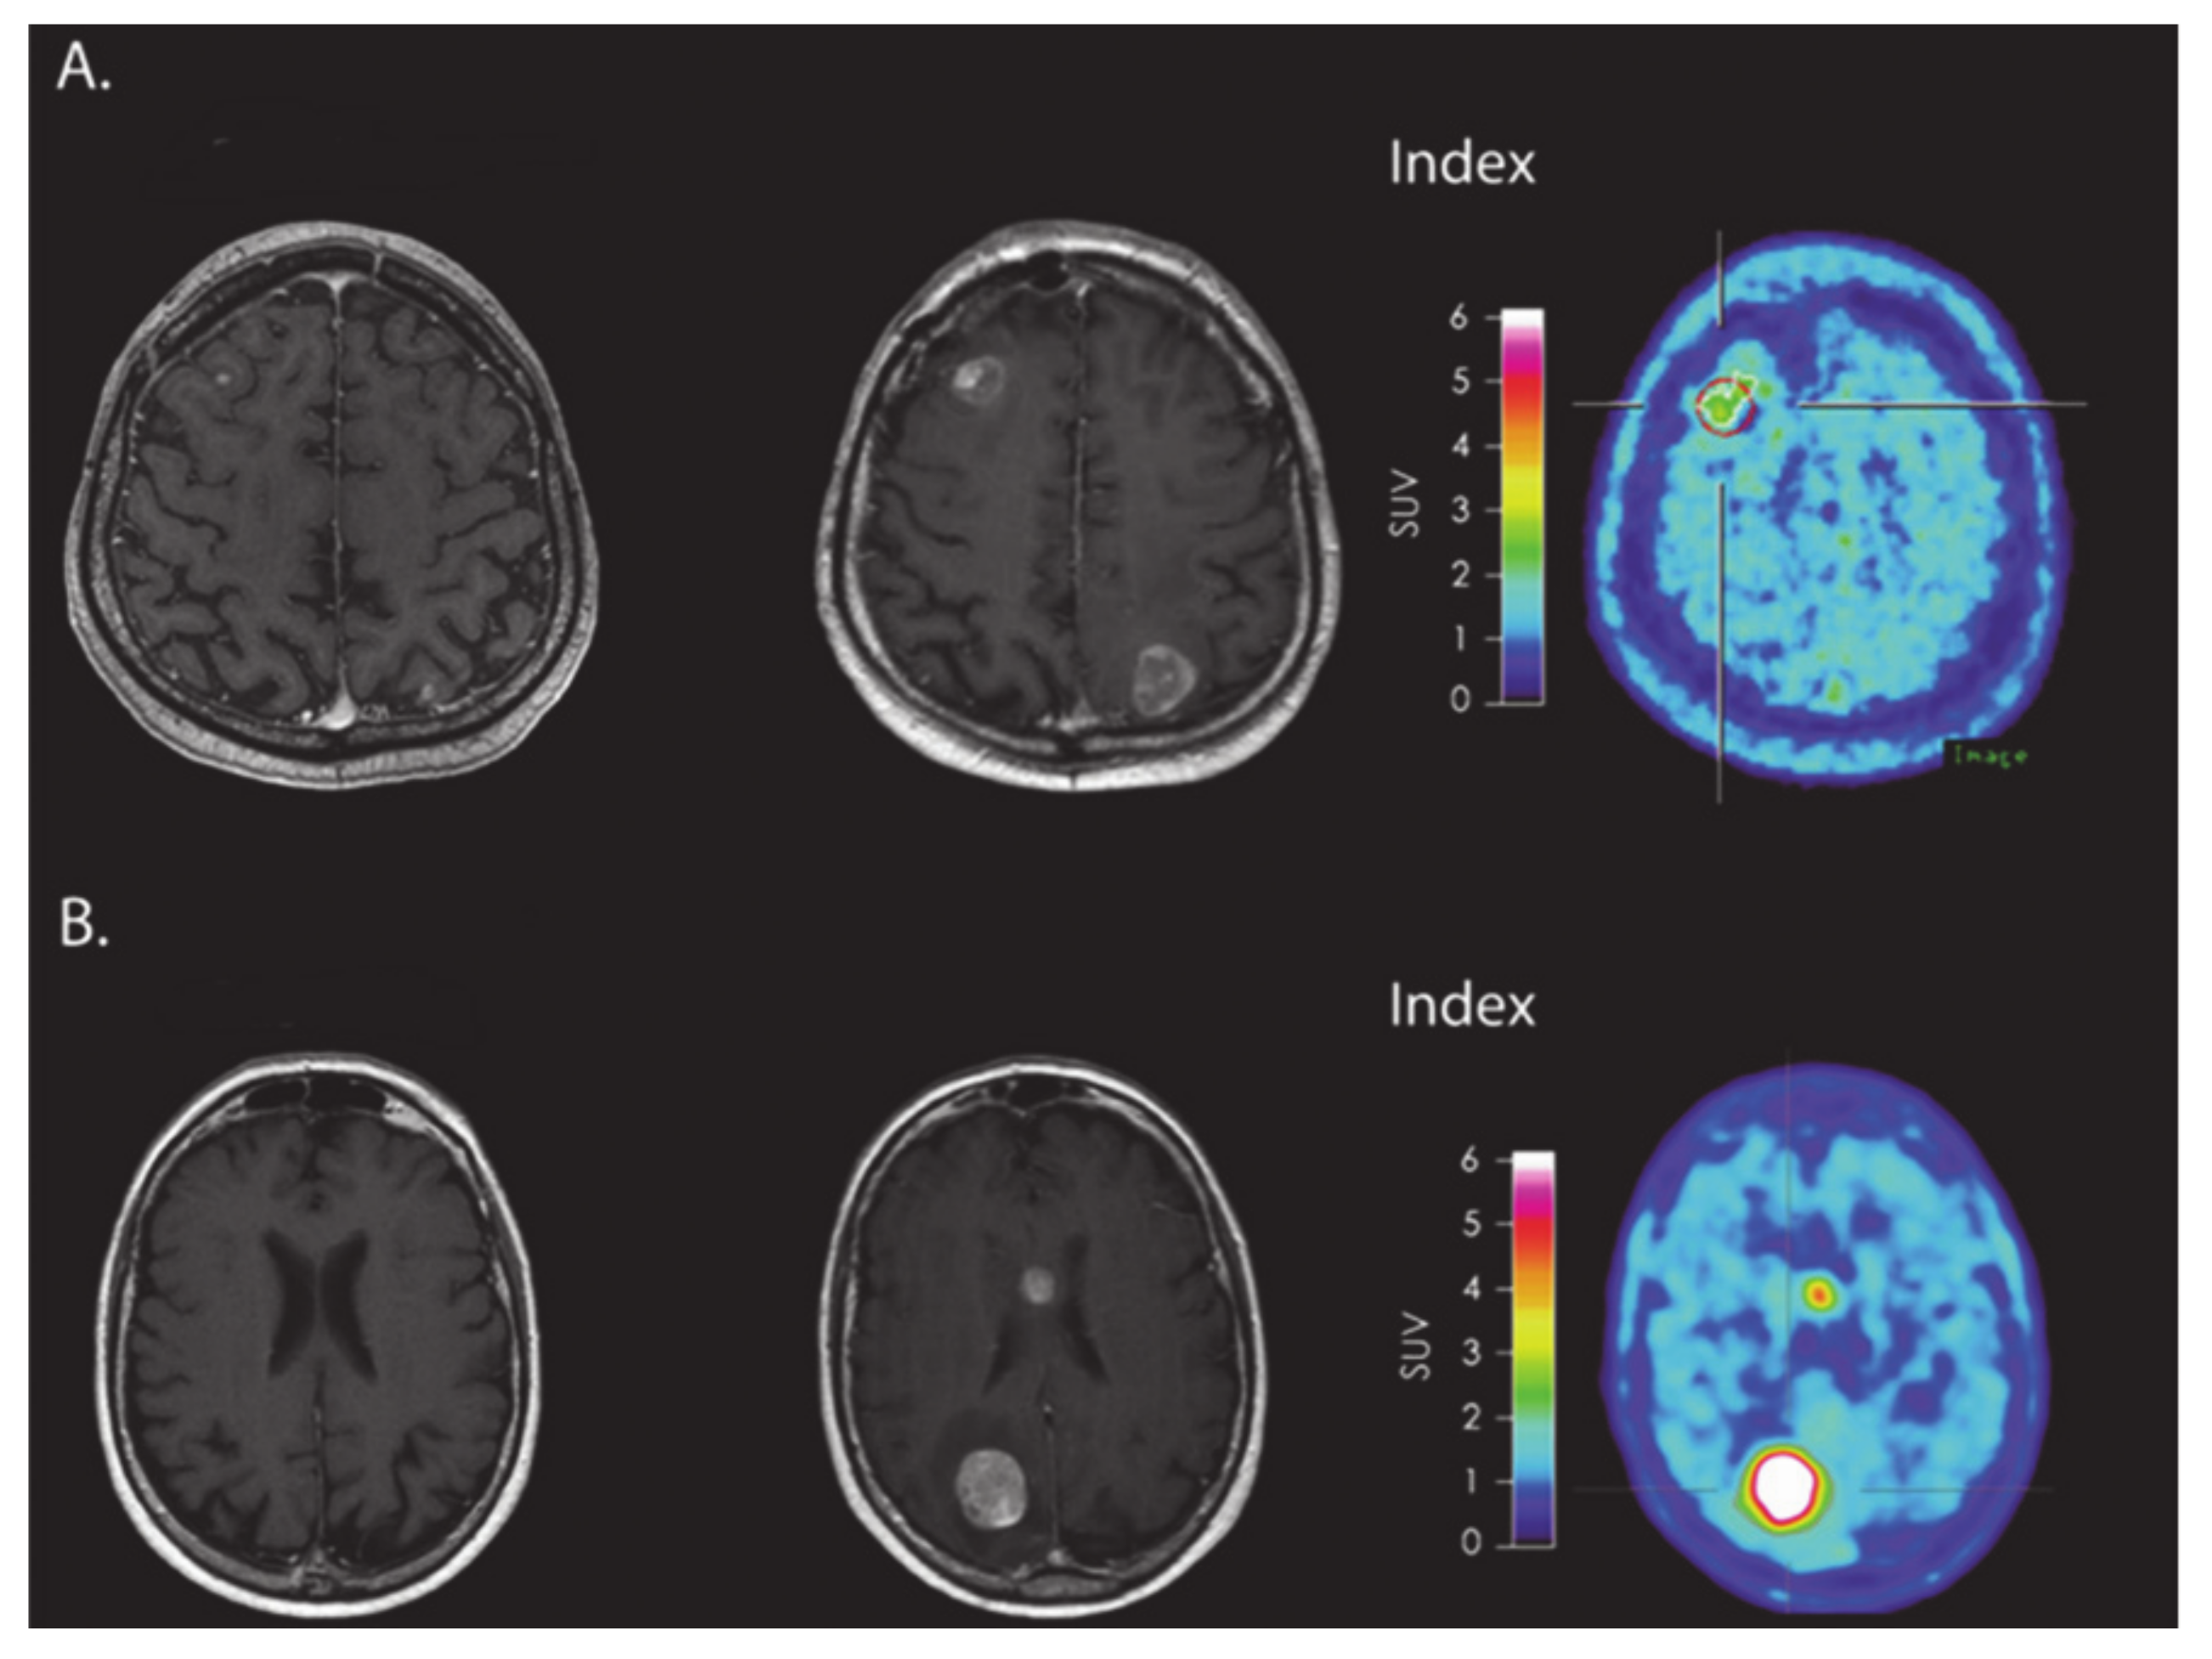

- Kebir, S.; Rauschenbach, L.; Galldiks, N.; Schlaak, M.; Hattingen, E.; Landsberg, J.; Bundschuh, R.A.; Langen, K.-J.; Scheffler, B.; Herrlinger, U.; et al. Dynamic O-(2-[18F]fluoroethyl)-L-tyrosine PET imaging for the detection of checkpoint inhibitor-related pseudoprogression in melanoma brain metastases. Neuro. Oncol. 2016, 18, 1462–1464. [Google Scholar] [CrossRef]

- Antonios, J.P.; Soto, H.; Everson, R.G.; Moughon, D.L.; Wang, A.C.; Orpilla, J.; Radu, C.; Ellingson, B.M.; Lee, J.T.; Cloughesy, T.; et al. Detection of immune responses after immunotherapy in glioblastoma using PET and MRI. Proc. Natl. Acad. Sci. USA 2017, 114, 10220–10225. [Google Scholar] [CrossRef]